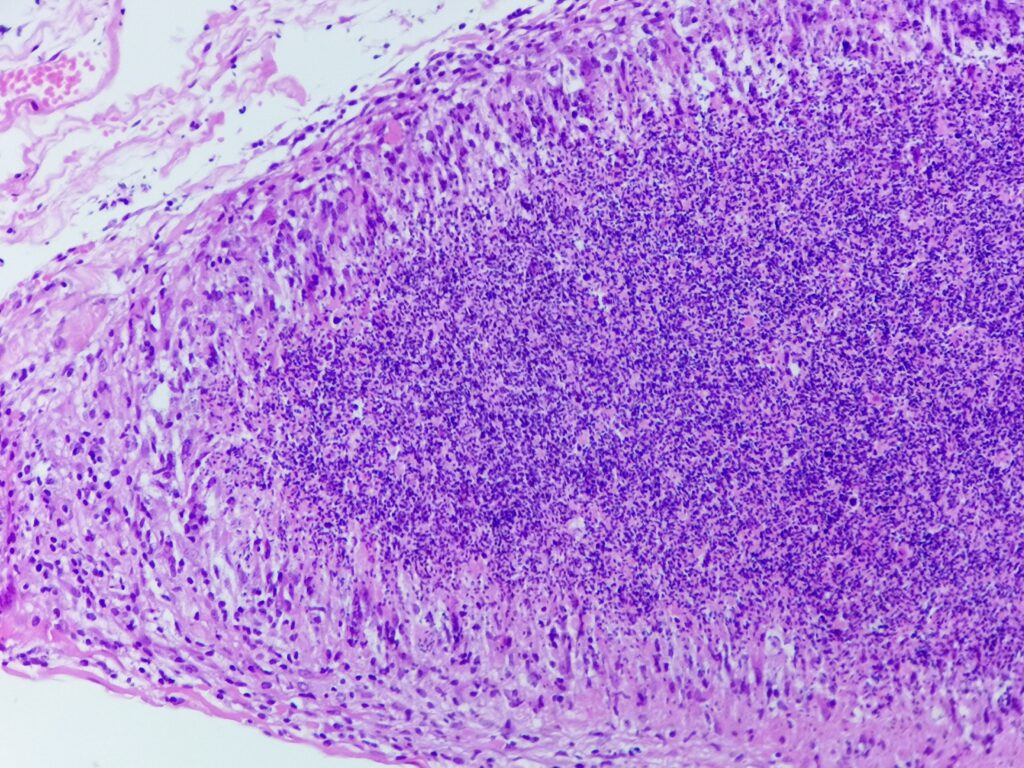

Obrazy mikroskopowe:

Cechy charakterystyczne:

- cienkościenna torbielowata struktura składająca się z tkanki łącznej (krzyżyk) wysłana jednowarstwowym nabłonkiem (czerwona strzałka) od kostkowego po walcowaty, z pojedynczymi komórkami rzęskowymi – torbiel nasienna patrz przypadek nr 105. SMP

- poza światłem zmiany obecne są plemniki (gwiazdka) z otaczającym odczynem z histiocytów (komórki o owalnym lub okrągłym jądrem komórkowym stosunkowo obfitej lekko kwasochłonnej cytoplazmie, niebieska strzałka), nieliczne limfocyty i komórki wielojądrowe (zielona strzałka) – ziarniniak

- brak komórek atypowych, martwicy centralnej, grzybów bądź innych mikroorganizmów

Ziarniniak nasienny (sperm granuloma)